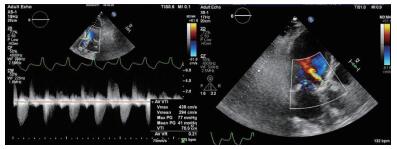

术后随访:患者术后病情稳定,病房继续住院3 d后顺利出院。术后1个月随访化验提示“proBNP 5 869 pg/mL,血肌酐185 μmol/L,肌钙蛋白T 0.118 ng/mL”,复查心超提示“LVEDD 5.19 cm,simpson's测得LVEF 58.6%;主动脉瓣口最大流速2.35 m/s,最大压差22 mmHg,平均压差10 mmHg,瓣口面积1.65 cm2”(图 4)。

| 图 4 患者术后1月随访超声心动图 |